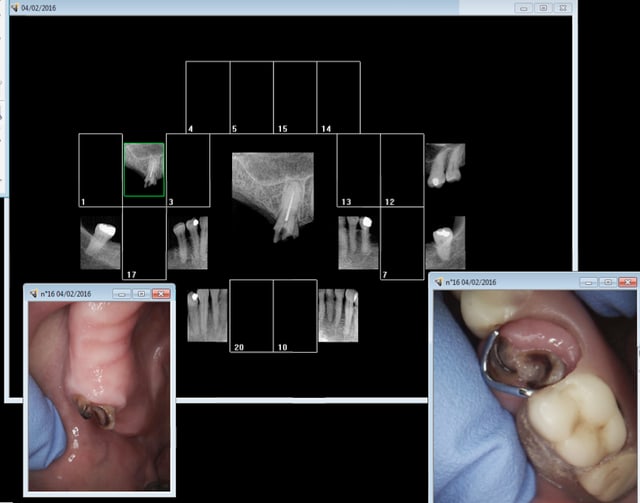

Bilan pré intervention en vue de la pose d'une prothèse de hanche. La patiente n'a pas voulu que je vire cette 16 because "ca tient l'appareil".